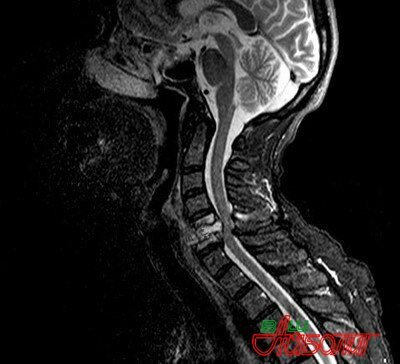

Влияние заболевания позвоночника на головной мозг  Головной мозг имеет двойственную связь со спинным мозгом, и эта связь осуществляется стволовой частью и корковой, как в нисходящем направлении, так и восходящем. Поэтому с помощью восходящих путей происходит передача импульсов в головной мозг, по нисходящим нервным окончаниях происходит передача эфферентным нейронам спинного мозга, команды от отделов головного мозга.

Все восходящие нервные окончания спинного мозга связаны с продолговатым мозгом, средним мозгом, зрительными буграми и вестибулярным аппаратом, обеспечивающего равновесие человека. Восходящие пути представляют собой белое вещество спинного мозга и от него отходят нервные окончания, которые иннервируют все органы, мышцы и ткани человека, по команде головного мозга. Необходимо отметить, что спинной мозг может выполнять две основные функции, это проводящая и рефлекторная и при этом рефлекторная способствует осуществлению простых рефлексов, это могут быть сгибание и разгибание верхних и нижних конечностей, но этот процесс, в то же время непосредственно контролируется мозгом. Все нервные импульсы, которые отходят от внутренних органов, мышц и кожи идут, как мы упоминали по белому веществу спинного мозга и они направлены в головной мозг. Все импульсы, которые идут от головного мозга, направлены к исполнительным нейронам спинного мозга, вот такая непосредственная происходит связь между головным и спинным мозгом. Поэтому существует непосредственное влияние заболевания позвоночника на головной мозг.

Все болевые ощущения, которые передаются в головной мозг через спинной, перерабатываются в отделах головного мозга и они даже могут остаться в его памяти в виде фантомных болей. Например, нога уже ампутирована, но мозг помнит боль этой части тела и в несуществующей ноге могут, как бы появиться боли, и человек начинает на нее жаловаться, что у него болит несуществующая стопа. Влияние заболевания позвоночника на головной мозг состоит в том, что при нарушении работы шейного отдела позвоночника, начинают мучить головные боли. Это связано с малоподвижным образом, увеличением давления на межпозвоночные диски, что приводит к сужению межпозвоночных щелей и при этом происходит передавливание нервных окончаний и кровеносных сосудов спинного мозга, но виновницей головной боли, может быть, излишний вес у человека, что приводит к ухудшению кровоснабжения и гипоксии головного мозга. При травматическом повреждении спинного мозга в результате перелома позвонка и при этом страдает головной мозг, в этом случае может нарушиться связь спинного и головного мозга. Человек утрачивает двигательные рефлексы и из спинного мозга в головной не поступает никакая информация о состоянии внутренних и других органов, которые иннервируются и управляются спинным мозгом. Кроме того головные боли могут быть при остеохондрозе, искривлении позвоночника, при сколиозе, а также в том случае, когда нарушается кровоснабжение головного мозга из-за шейного остеохондроза. Это связано с тем, что две позвоночные артерии, которые проходят между позвонками, начинают пережиматься за счет оттока тканей вокруг позвоночника, и развивается пульсирующая боль, может подняться кровяное давление и даже развиться мигрень.

Нарушение шейного отдела связано с нарушением работы головного мозга, при нарушении работы спинного мозга начинаются головокружение, и головные боли, а также может развиться цервикокраниалгия. Это головная боль, которая связана шейным отделом позвоночника и боль распространяется в лобно-височную область, но часто переходит в затылочную область и такие боли могут длиться от нескольких часов до нескольких дней, в том случае, когда не проводится лечение позвоночника, такая боль становится хронической. Головные боли могут возникать при сильных рефлекторно-мышечных напряжениях, но и могут быть на почве психогенных симптомов. Необходимо отметить, что весь наш организм связан нервной системой и во главе всего стоит головной мозг, который непосредственно связан со спинным мозгом, поэтому. Любые заболевания в спинном мозге, начинают отражаться на работе головного мозга и это связано с тем, что их объединяют функциональная работа всех органов и систем в организме человека. В том случае, когда нарушается работа какого-то отдела позвоночника, то мозг берет на себя эти функции и в итоге может не прекращаться работа этого органа. Поэтому можно сделать однозначный вывод, что в том случае, когда будет здоров позвоночник, то будет хорошо работать головной мозг, следовательно, у человека будут нормально работать все органы и он будет здоровым.